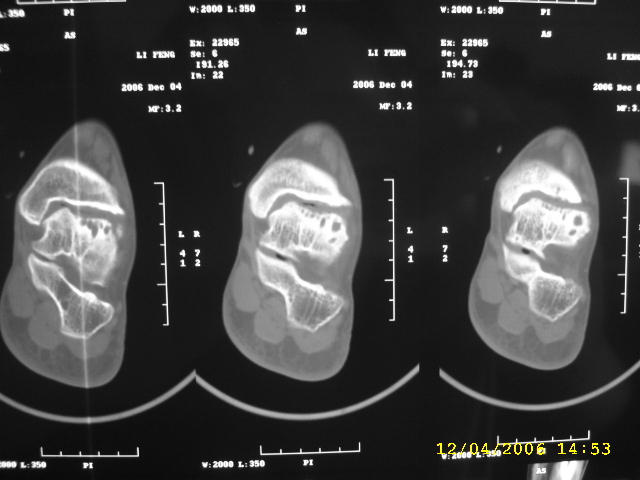

男,44,双踝关节肿胀,疼痛,活动受限2月余。无外伤史。

双侧距骨及胫骨都有骨质破坏,还很对称,最好追问一下病史,看这人有没有痛风。

双侧距骨可见多发囊变区,边缘硬化内可见更高密度影,考虑1双侧踝关节结核2退行性骨关节病

双侧距骨关节面下可见多发囊变区,边缘硬化内可见更高密度影。考虑:双踝剥脱性骨软骨炎。

双侧距骨及胫骨都有骨质破坏,边缘硬化内可见更高密度影,双侧对称性发病,踝关节及跟距关节内低密度影(气体影?),双侧对称发病基本可以排除关节结核及化脓性关节炎,痛风性关节炎以第1跖趾关节为典型发病部位,临床症状间歇性发作,受累关节非对称性肿胀与本例不符,首先考虑退行性骨关节病,请结合抗\"o\"及类风湿因子检查排除风湿性关节炎。

跟进!关节间隙明显变窄,诸相对骨性关节面增生、硬化,内见多发囊变,考虑增生性骨关节病!

双侧距骨及胫骨近关节面都有骨质破坏,边缘硬化,唇样变,内可见囊状低密度影,双侧对称性发病,首先考虑退行性骨关节病。